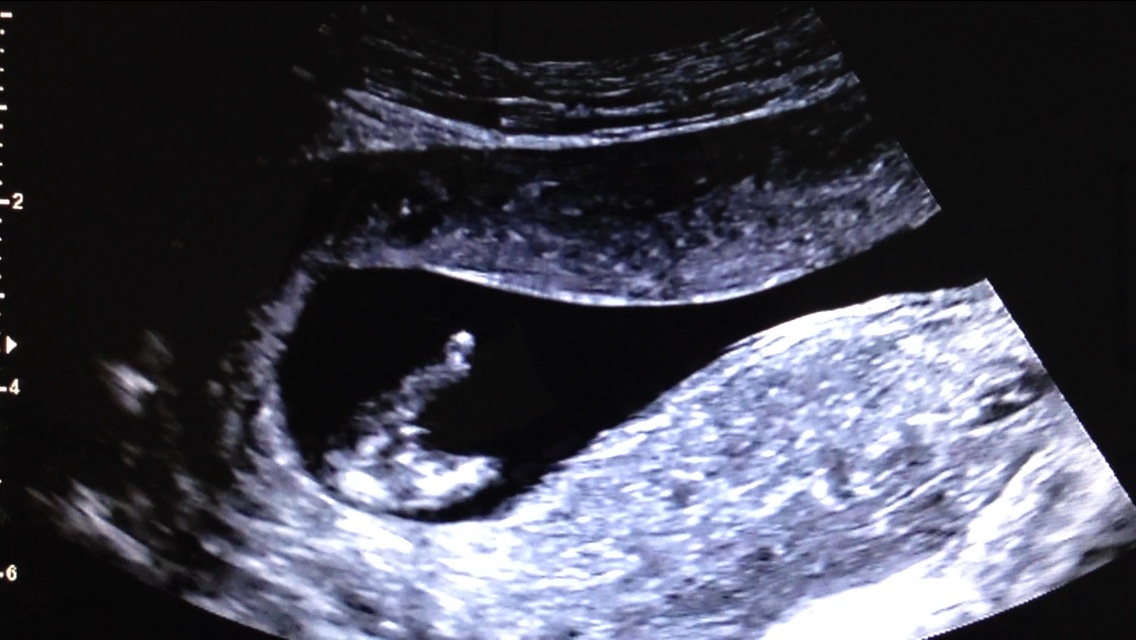

Last one!Attachment 20332

Thank you!! I can't believe I might have a boy in there after 3 girls! Here are two more.. Does anyone see anything girly at all in these?? So hard to not get excited yet :). Attachment 20339

I'd be very, very hopeful for blue with these pictures. The nub pics are stacked almost vertical and the potty shot pics, although mighty early, are showing a good deal of parts that look boyish. With both pointing the same direction, I'd be cautiously thinking blue for you :)

Leaning boy